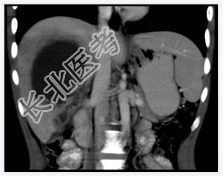

- [材料题] 患者男性,25岁,因发热.肝区疼痛2周入院。2周前患者无明显诱因出现高热.肝区疼痛,血常规检查白细胞及中性粒细胞明显升高。体查.肝肋缘下1cm可触及,且有明显触痛。行上腹部CT增强扫描+三维重建。

- 简答题1、患者的诊断及依据是什么?

- 简答题2、鉴别诊断有哪些?